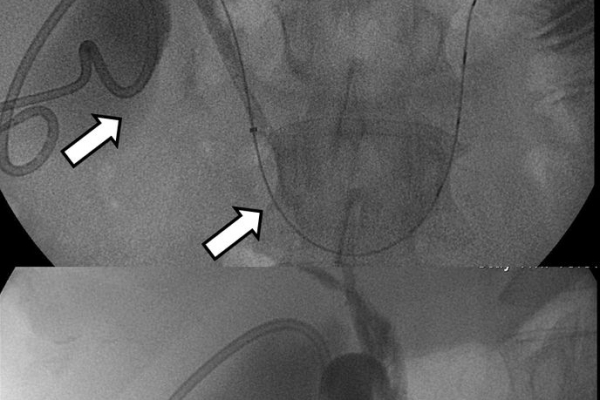

Η παροχέτευση των χοληφόρων σε αυτές τις περιπτώσεις θα πρέπει να γίνεται άμεσα, είτε ταυτόχρονα προς τα έξω και προς το 12κτυλο (έσω-έξω παροχέτευση), είτε μόνο προς τα έξω με τη βοήθεια pigtailκαθετήρα (εξωτερική παροχέτευση)

Σε περιπτώσεις όπου υπάρχει απόφραξη των χοληφόρων και ενδείκνυται η τοποθέτηση ενδοπρόθεσης (stent), τότε η βατότητα των χολαγγείων και η αντιμετώπιση του αποφρακτικού ικτέρου μπορεί να διασφαλιστεί με την τοποθέτηση ενδοπροθέσεων (stents).